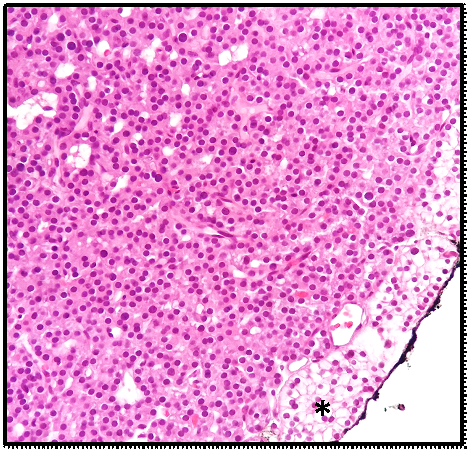

From the study of hypercalcemia with hyperparathyroidism, a cervical ultrasound was performed which confirmed the presence of a nodule suggestive of left parathyroid adenoma (Figure 1) coinciding with the focus of uptake on sestamibi scintigraphy (Figure 2). Primary hyperparathyroidism with hypercalcemia was identified, which could justify the overall clinical picture. The recent worsening of behavioural changes and mental confusion were also interpreted in the same context. A month later, patient underwent left lower parathyroidectomy (Figure 3), and histology revealed parathyroid adenoma (Figure 4).

Figure 1 Cervical ultrasound showing a hypoechogenic nodular structure (20x9mm) posterior to the left lobe of the thyroid, compatible with parathyroid adenoma.